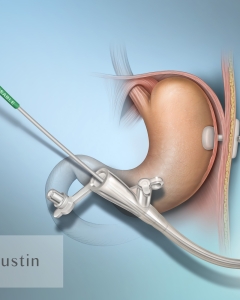

Internal Art Medical Illustration

Blending Art, Anatomy and Science for Creative Visuals

Welcome to my Patient and Professional Marketing page, where I harness the power of anatomical illustrations to educate and empower both patients and medical professionals. My unique approach combines artistry and education to convey complex surgical procedures and the utilization of medical devices in an easily understandable manner.